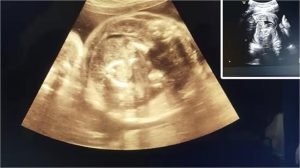

महाराष्ट्र के बुलढाना जिले के एक सरकारी अस्पताल में एक दुर्लभ चिकित्सा मामला सामने आया, जिसने डॉक्टरों को भी हैरान कर दिया। जिले के मोताला तहसील से आई 32 वर्षीय गर्भवती महिला की सोनोग्राफी के दौरान डॉक्टरों ने पाया कि उसके गर्भ में पल रहे बच्चे के पेट में भी एक भ्रूण मौजूद है।

डॉक्टर प्रसाद अग्रवाल ने सोनोग्राफी करते समय इस असामान्य स्थिति को देखा, जिसके बाद उन्होंने दोबारा जांच की और अपने वरिष्ठ डॉक्टरों को जानकारी दी। महिला को किसी भी प्रकार की जटिलता से बचाने के लिए तुरंत संभाजीनगर रेफर कर दिया गया।

इस स्थिति को चिकित्सा जगत में Fetus in Feto कहा जाता है, जो बेहद दुर्लभ मामला है। सिविल सर्जन डॉ. भागवत भुसारी के अनुसार, दुनियाभर में अब तक ऐसे लगभग 200 मामले सामने आ चुके हैं, जिनमें से भारत में केवल 15 से 20 ही दर्ज हुए हैं। विशेषज्ञों का कहना है कि मां को कोई खतरा नहीं होगा, लेकिन नवजात के लिए जल्द से जल्द उपचार आवश्यक होगा ताकि उसकी सामान्य वृद्धि प्रभावित न हो।